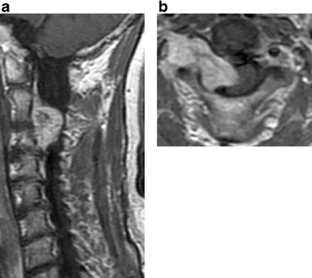

Patients included 6 men and 13 women, with a mean age at the time of surgery of 48.3 years (range, 25–70 years). Underlying pathologies included 16 schwannomas, 2 neurofibromas, and 1 double tumor (schwannoma and meningioma). According to Eden’s classification, one patient was classified as Type 1, 5 as Type 2, 8 as Type 3, and 5 as Type 4. In 13 cases, tumors were excised through the posterior approach alone, compared to five cases using the anterior approach. One case was excised using combined anterior and posterior approaches. Facetectomy was not performed in 18 cases. In one case, the facet joint on one side had already destroyed and needed instrumentation. Tumors were totally excised in all cases. Postoperatively, the patients did not display any further neurological deficit, with the exception of transient radiculopathy in two patients. Major surgical complications and cerebrospinal fluid leakage were not seen. Tumor recurrence and spinal segmental instability were not found during follow-up period (mean, 41.6 months).

Dumbbell tumor surgery requires sufficient debulking of the epidural and paravertebral mass, using intraoperative nerve stimulation and Doppler ultrasonography to detect the vertebral artery. When using a posterior approach, recapping laminoplasty using an ultrasonic bone curette is very useful to remove tumor without sacrificing facet joints.